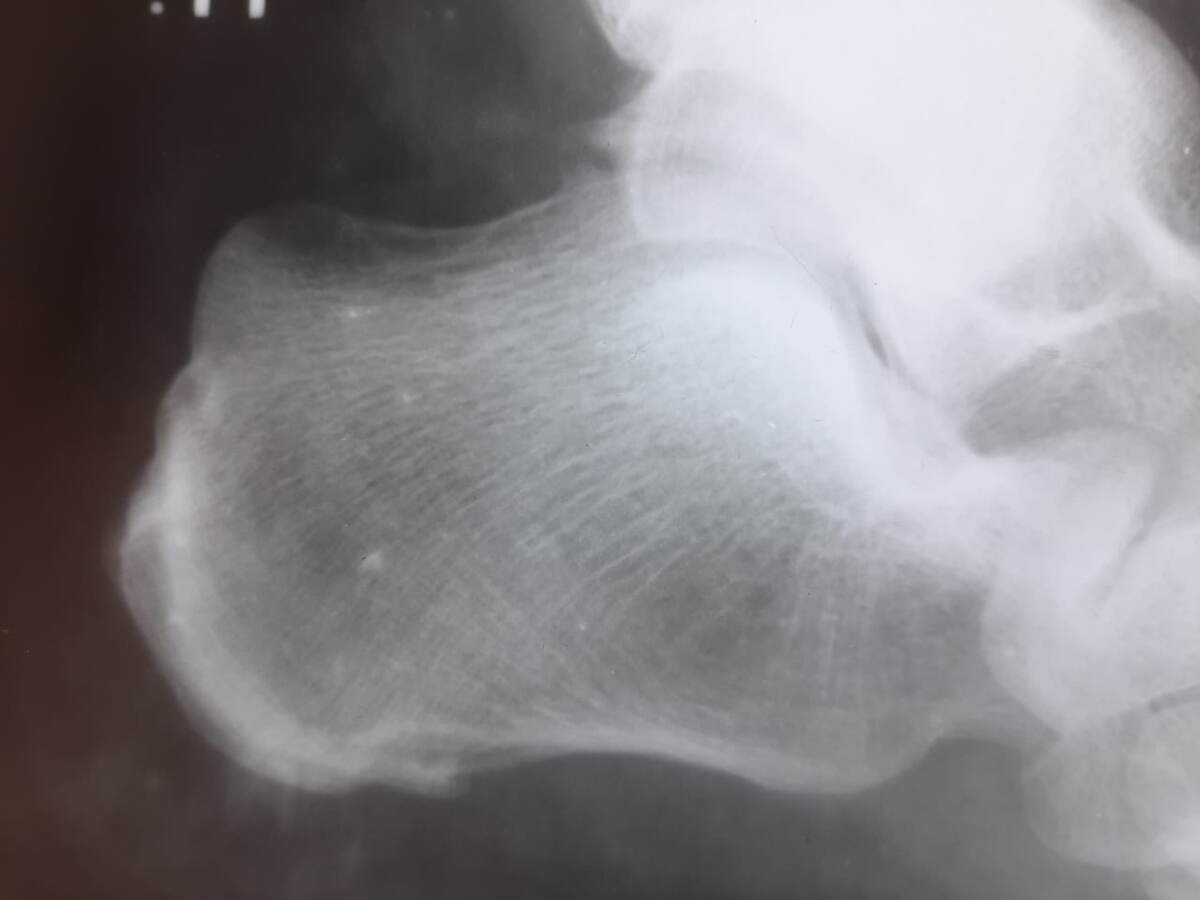

Уколом в пятку обычно называют лекарственное введение стероидных препаратов. Как правило, его назначают при возникновении боли. Как правило, при пяточной шпоре ( от чего возникает пяточная шпора, я писал в этой статье). Блокады или уколы делаются с целью снять воспаление и боль.